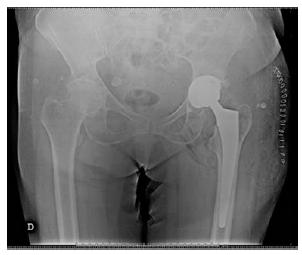

A admissão no serviço de Ortopedia do Centro Hospitalar ocorreu a 19/11/2020, com o diagnóstico de coxartrose esquerda, para cirurgia eletiva, que só se viria a realizar a 21/11/2020. Em relação aos exames pré-operatórios, foram realizadas análises sanguíneas, que se encontravam dentro dos valores de referência; eletrocardiograma, com ritmo sinusal; e radiografia do tórax e bacia (Figura 1). A senhora foi também submetida a uma avaliação por parte do anestesista, obtendo um risco cirúrgico de ASA II (American Society of Anestesiology), indicativo de doença sistémica leve. No dia 21/11/2020, foi submetida a artroplastia total da anca esquerda, sob raquianestesia, tendo o pós-operatório decorrido sem intercorrências e com controlo radiográfico da bacia após a cirurgia (Figura 2).